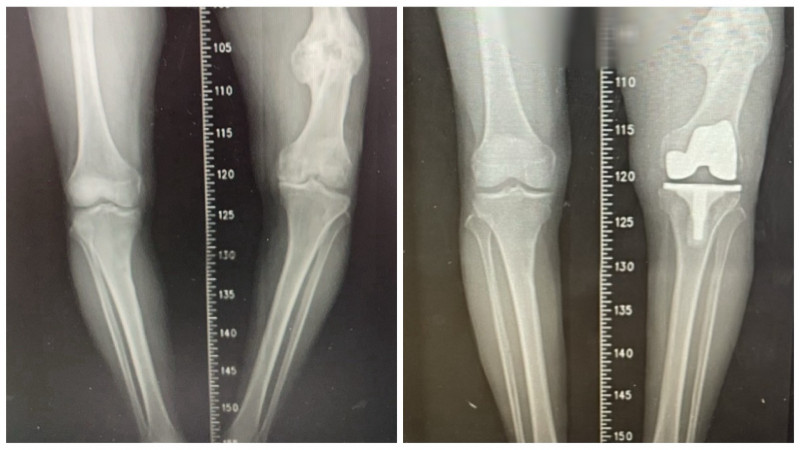

〔記者歐素美/台中報導〕台中市豐原區一名87歲黃姓老翁,年輕時左側股骨骨折,當時治療不佳,導致骨癒合不良並出現內翻變形,最初兩下肢僅有約 2 公分長度差距,隨著時間推移逐漸惡化,最後擴大至近7公分,長年深受長短腳與膝蓋疼痛所苦,不僅步態不穩,更引發腰部與下肢不適,經衛生福利部豐原醫院骨科醫師江福財進行人工膝關節置換手術,成功改善症狀,重拾穩健步伐。

黃翁手術困難度在於要同時面對「陳舊性股骨骨折造成的骨骼變形」與「長達 7 公分的下肢長度差距」,因此,除了進行人工關節置換,還需進行精準的韌帶平衡,經輔以電腦導航與影像輔助技術,在修正骨骼角度的同時兼顧關節周圍韌帶平衡,避免造成膝關節不穩定,行動困難。

江福財表示,黃翁手術並未採用截骨矯正方式,而是單靠人工膝關節置換,直接解決患者最在意的長短腳問題,最終成功將雙腿長度差縮小至約 2.5 公分,大幅改善步態,術後患者無需輔具即可下床行走,逐步恢復生活自理能力,術後必須持續進行肌力訓練與步態矯正,以確保關節穩定性,並定期回診追蹤,以獲得最佳治療成效。